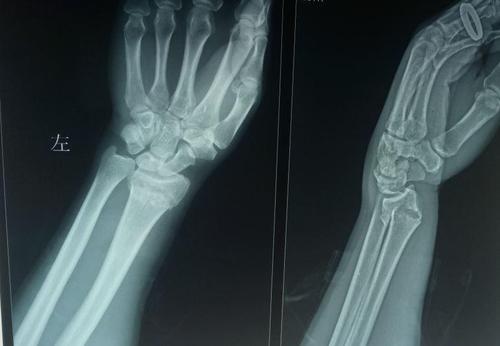

桡骨远端骨折

左手桡骨错位骨折

左桡骨远端骨折

左尺桡骨远端骨折图片

左手桡骨远端骨折图

左侧桡骨远端骨折图片